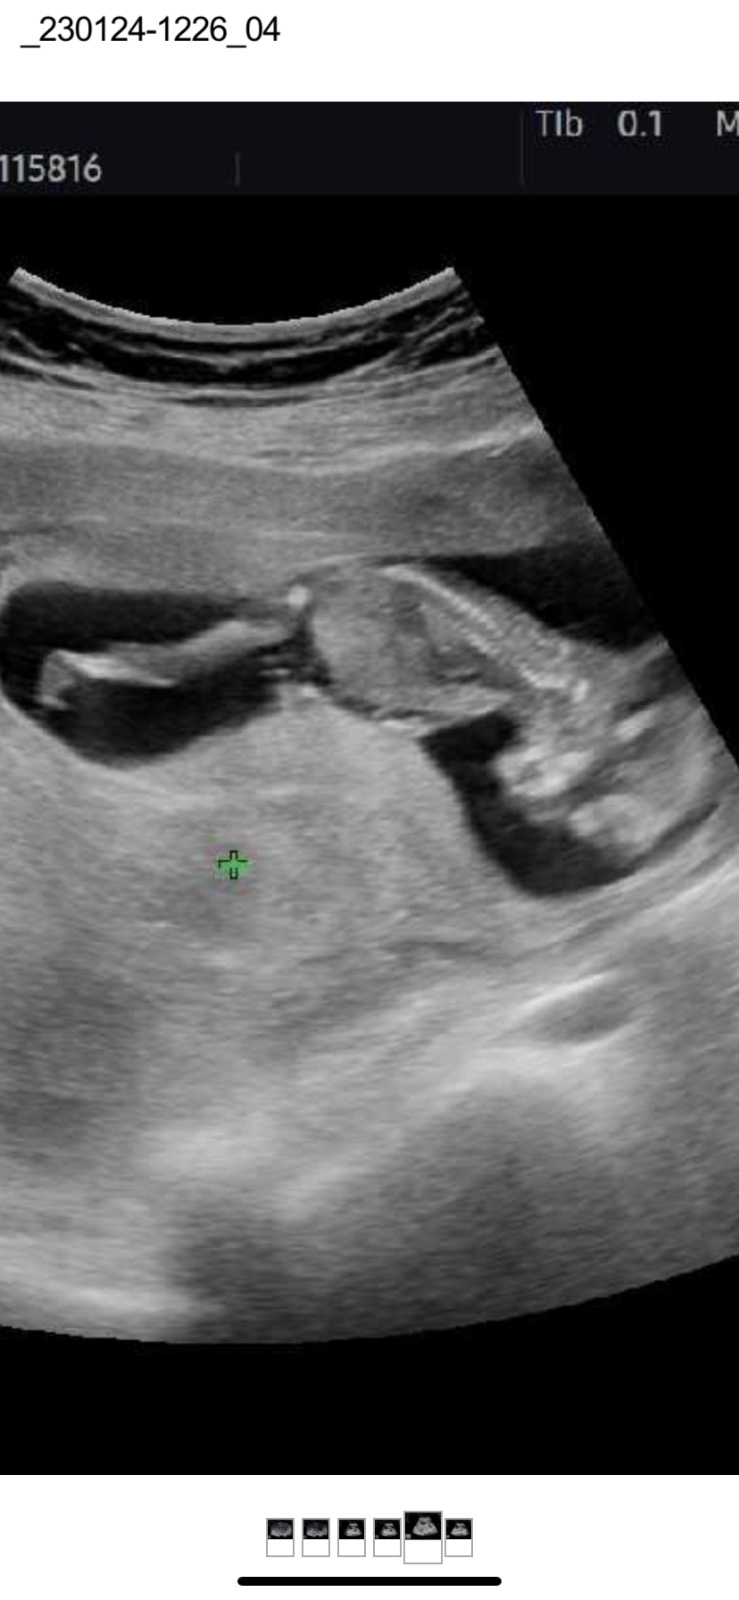

@simca1998 😊 krásný termín, na Aničku 😁 to mám narozeniny 🤣 a nádherná fotečka, fakt se povedla 😍